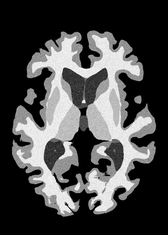

4.2 Registration to a 100 micron ex-vivo brain MRI volume

To showcase the efficacy of our method on real large scale images, we register a 250 in-vivo MRI image (Lüsebrink et al., 2017) to a 100 ex-vivo FLASH human brain volume (Edlow et al., 2019). This represents an inverse problem with more than 11.2B optimizable parameters (compared to 20M for clinical datasets), or 44.8GB of GPU memory. The entire problem does not fit on most GPUs, necessitating distributed multimodal registration. We optimize a composite transform - affine followed by a diffeomorphic mapping; details can be found in Section E.1. Multimodal deformable registration took 58 seconds on 8 NVIDIA A6000 GPUs, which is unprecedented at this resolution. Fig. 6 shows qualitative results, highlighting the ability to register highly detailed structures such as cerebellar white matter; these structures are not visible at macroscopic scales. The resultant advantages of performing registration at this scale can allow researchers to characterize the neuroanatomy at microscopic resolutions and allow morphometric analysis of cortical layers and subcortical nuclei among other structures.